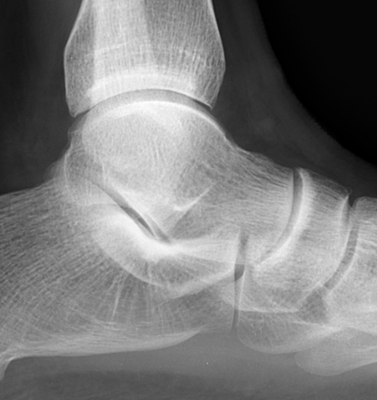

One normal ankle radiograph (A), and one abnormal ankle radiograph (B) revealing a moderate effusion. The teardrop shaped density seen extending anteriorly from the ankle joint along the neck of the talus has been referred to as the "teardrop sign" of ankle effusion. This is a useful sign in the diagnosis of ankle joint effusion, and may alert the diagnostician to possible underlying pathology.

Lateral normal ankle - Click on the image for a larger versionALateral ankle - Click on the image for a larger versionB